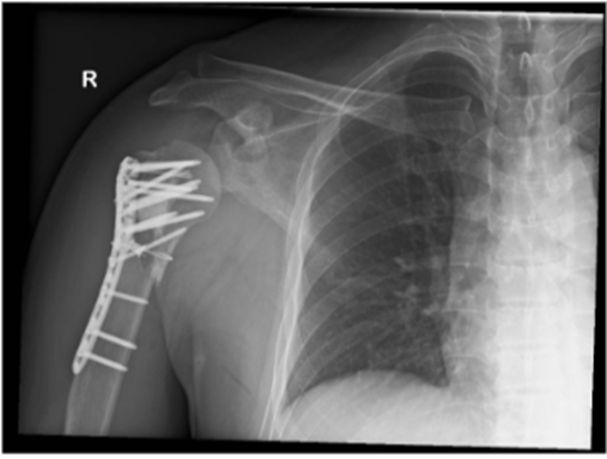

Image 3: Immediate postoperative radiographs of the right shoulder.

A. Anteroposterior (AP) view

B. Valpeau view

C. Lateral/ Y scapula view